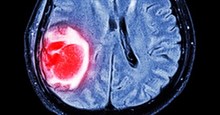

Giáo sư Peter J. Sadler, và nhóm của ông tại Khoa Hóa học đã chứng minh rằng hợp chất hữu cơ - kim loại có tên là Organo-Osmium FY26 - lần đầu tiên được phát triển tại Đại học Warwick có khả năng định vị, nhận dạng và tấn công vào các điểm yếu nhất của tế bào ung thư.

Hợp tác với Quỹ Phóng xạ Châu Âu, các nhà nghiên cứu đã phân tích rõ những tác động cụ thể của Organo-Osmium FY26 trong tế bào ung thư buồng trứng dưới ánh sáng huỳnh quang Tia X để theo dõi cách thức hoạt động của hợp chất này.

Kết quả cho thấy, tế bào ung thư dưới công nghệ nano được phát hiện rõ từng chi tiết, từng phút một. Họ cũng nhìn thấy được các ti thể, các hạt nhân chuyên cung cấp năng lượng cho tế nào ung thư hoạt động.

Nhóm nghiên cứu chỉ ra rằng, trong tế bào ung thư vẫn có những đột biến ADN trong ty lạp thể của tế bào ung thư khiến vị trí này rất yếu ớt và rất dễ bị tấn công.

Chất FY26 có trong Organo-Osmium FY26 đã tìm tới các ti lạp thể bị đột biến, từ đó len lỏi vào lỗ hổng này và phá hủy chức năng sống của tế bào ung thư ở thời điểm tế bào yếu nhất.

Không những thế, các nhà nghiên cứu cũng đã nhìn thấy các kim loại tự nhiên được sản xuất bởi cơ thể như kẽm và canxi di chuyển xung quanh các tế bào ung thư. Canxi được đặc biệt biết đến có khả năng ảnh hưởng đến chức năng của các tế bào ung thư, và người ta cho rằng kim loại tự nhiên này đã giúp chất FY26 đạt được một vị trí tối ưu trong tế bào ung thư để tấn công.

"Dưới chùm tia X-ray cao cấp tại ESRF, cuộc thí nghiệm đã cho chúng ta xác định rõ vai trò “không tưởng” của FY26 với độ phân giải rõ nét, trong đó, sự có mặt của các kim loại tự nhiên như kẽm, canxi cũng được phát hiện quanh tế bào ung thư. Điều này sẽ là tiền đề quan trọng mới để phát hiện và điều trị ung thư trong thời gian tới”.